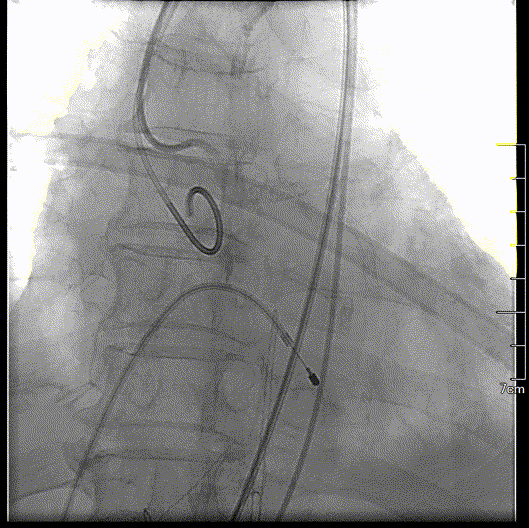

主动脉根部造影

球囊预扩,确认冠脉风险

瓣膜初始定位

瓣膜释放到可回收临界点

临界点处造影

瓣膜完全释放过程

瓣膜完全释放形态良好

工作钢丝送入左室进行起搏,180bpm起搏下预扩张主动脉瓣,完全扩张后,主动脉根部造影无反流,回撤球囊停止临时起搏。